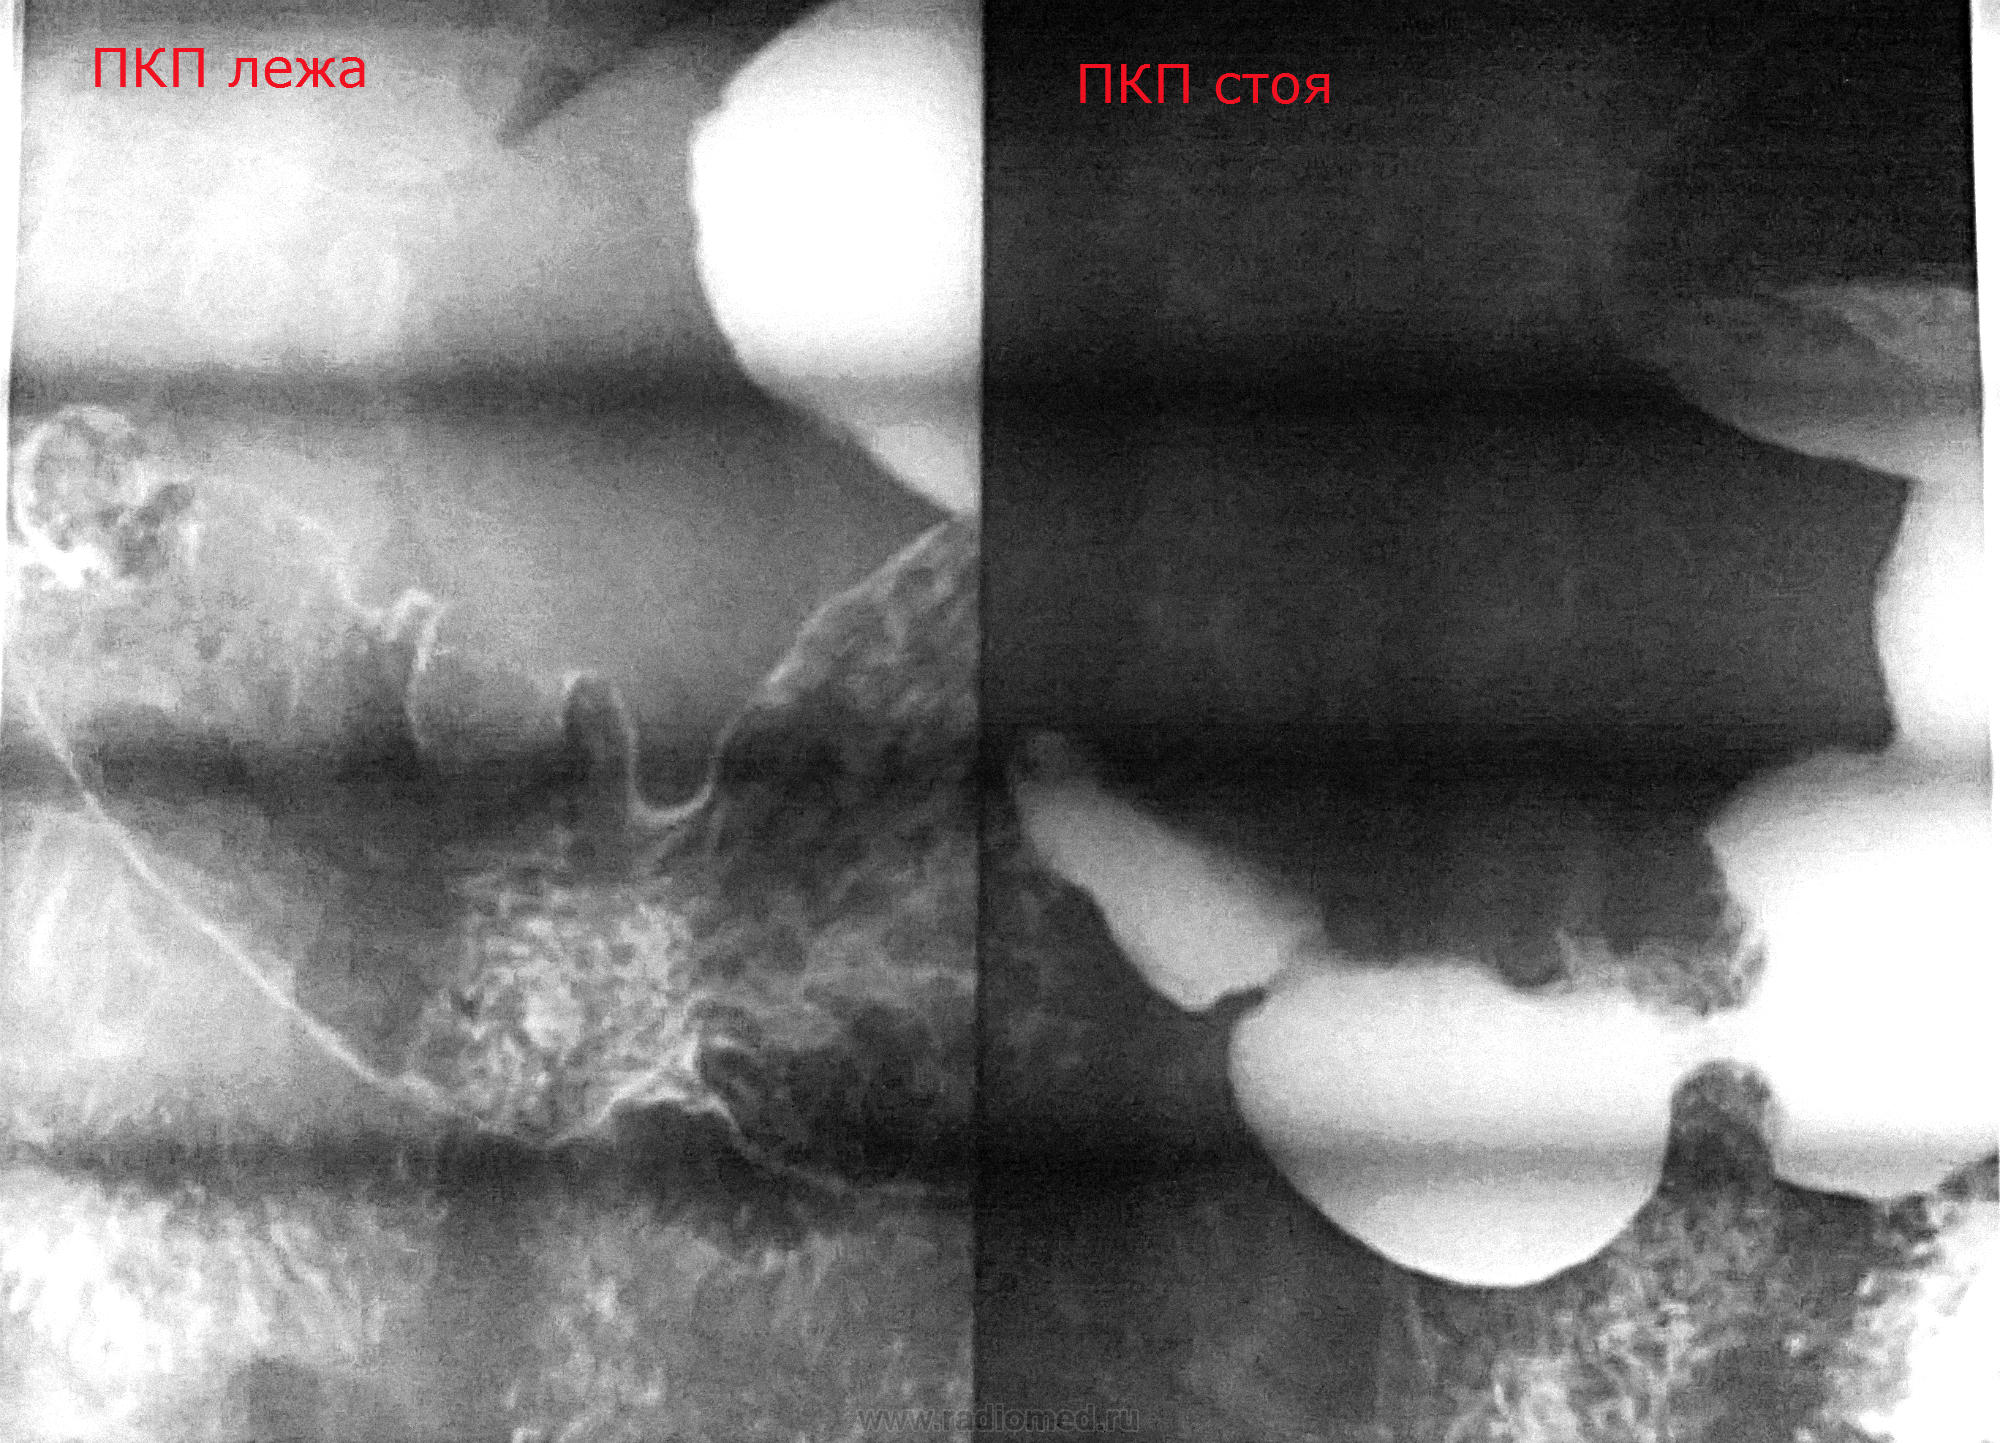

Мужчина 1963 г.р. Обратился с гастралгией к терапевту впервые за 15 лет (ранее по ФЭГДС единожды была язва малой кривизны тела желудка). Выполнена ФЭГДС (экзофитное бугристое серо-розовое плотное новообразование угла и малой кривизны антрума с рыхлой поверхностью, сплош покрытой детритом и белям налетом). Цитология - детрит, сплош мицелий грибка. Гистология отдана на руки (к онкологу). На рентгеноскопии - это. Стенка в зоне "бугоров" ригидна, аперистальтична.

Прошу прощения за полосы: частота матрицы камеры телефона на частоту ламп негатоскопа дает бегущую стриарность во всех положениях.

Рентгенологически экзофитный рак. Но меня совсем сбивает с толку грибок в желудке...

Извиняйте за молчание - не каждый день, а то и месяц могу отдохнуть на сайте... Так как я узурпировал в своем районе всю рентгенологическую и эндоскопическую власть в своих одних руках, мое заключение всегда носит комплексный характер, то бишь сам себе вразрез идти не могу. Посему эндоскопически: экзофитное новообразование угла желудка с распадом, подозрение на желудочный рак; рентгеноскопически: suspitio c-r antri ventriculi, смешанная форма роста. Suspitio - потому что без окончательной верификации.